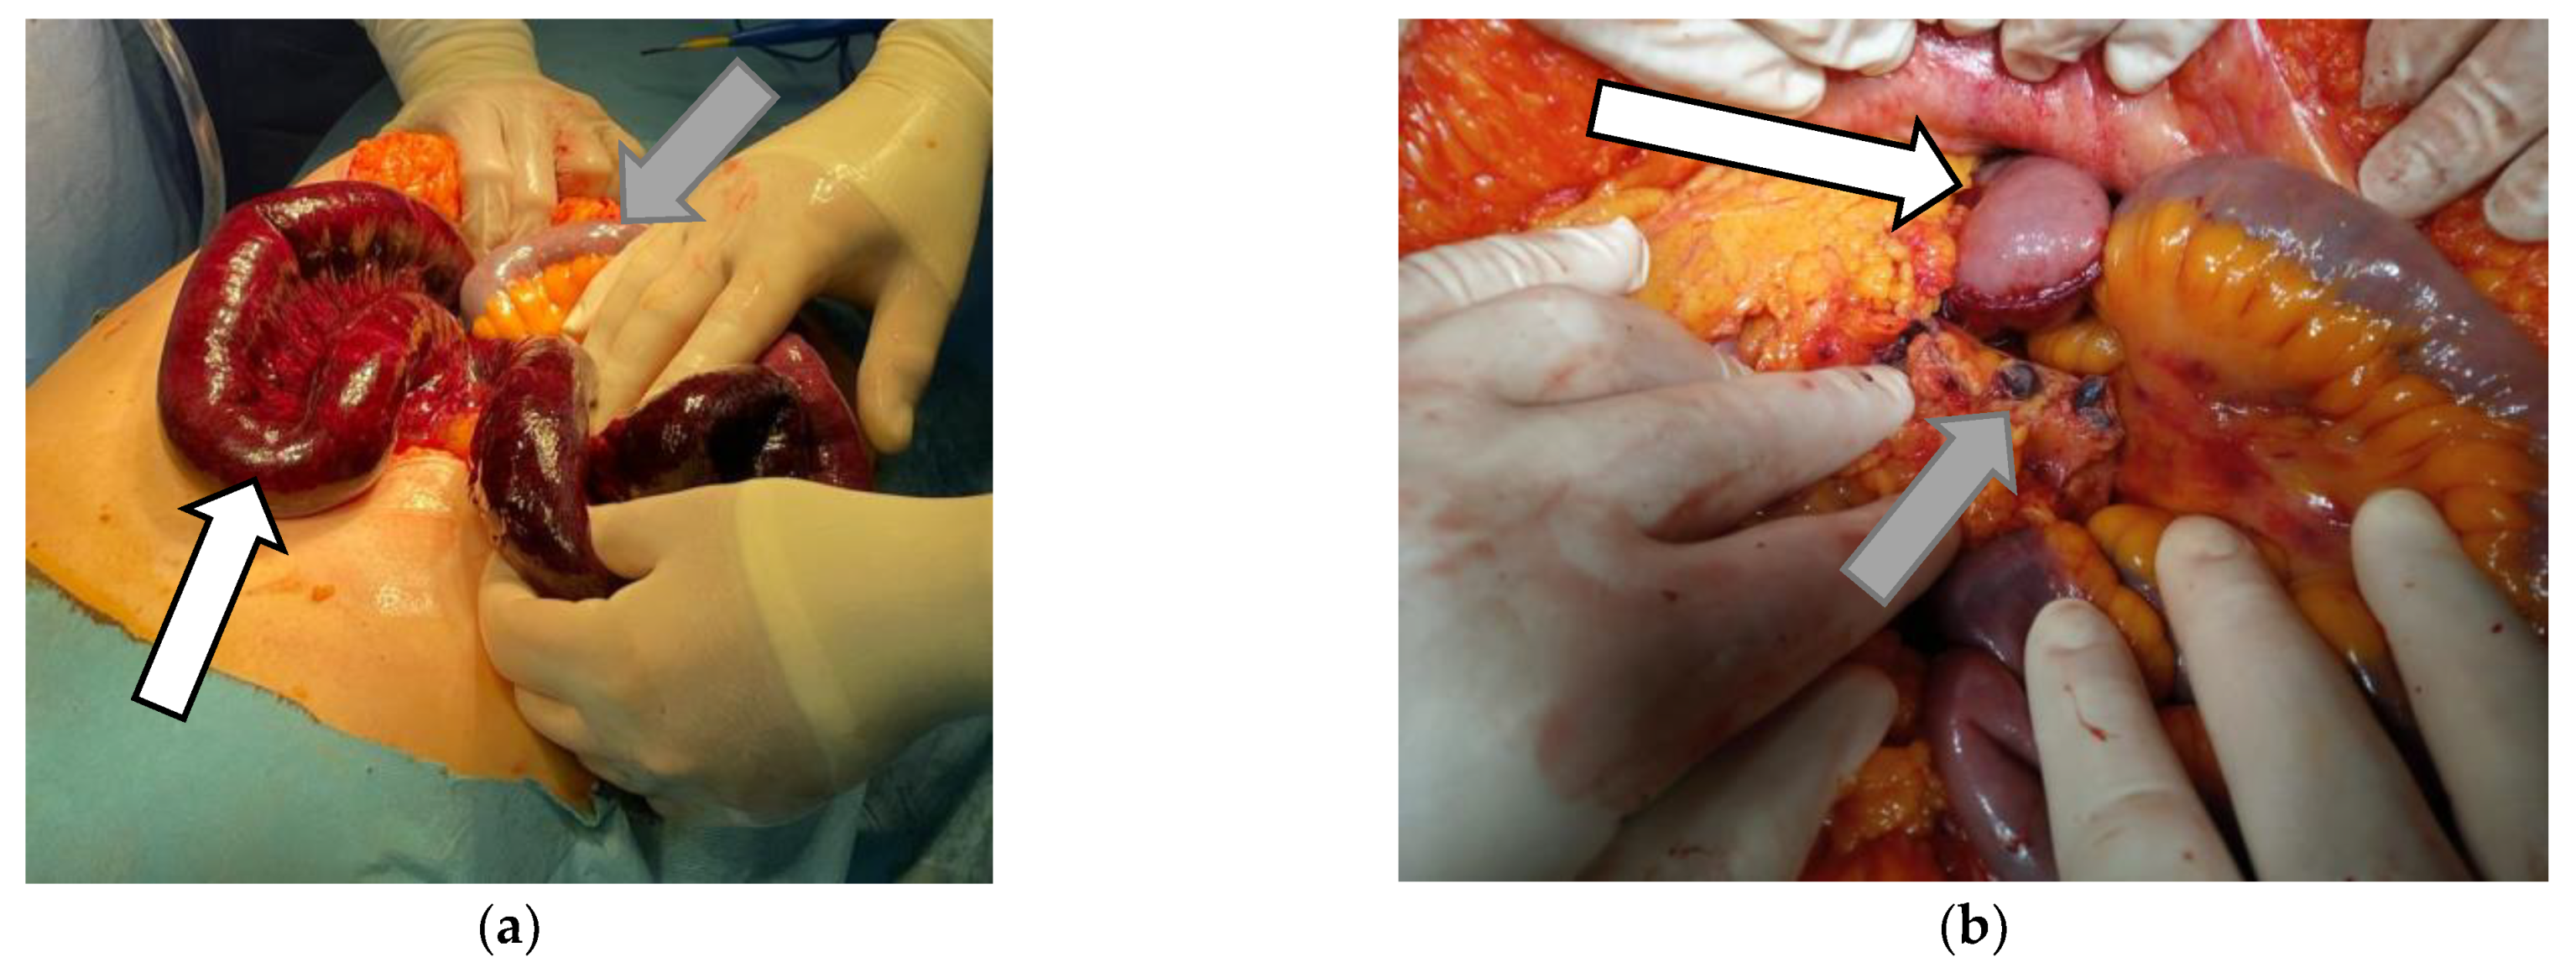

Portal Vein and Mesenteric Artery Thrombosis Following the Administration of an Ad26.COV2-S Vaccine—First Case from Romania: A Case Report

2. The Case Presentation